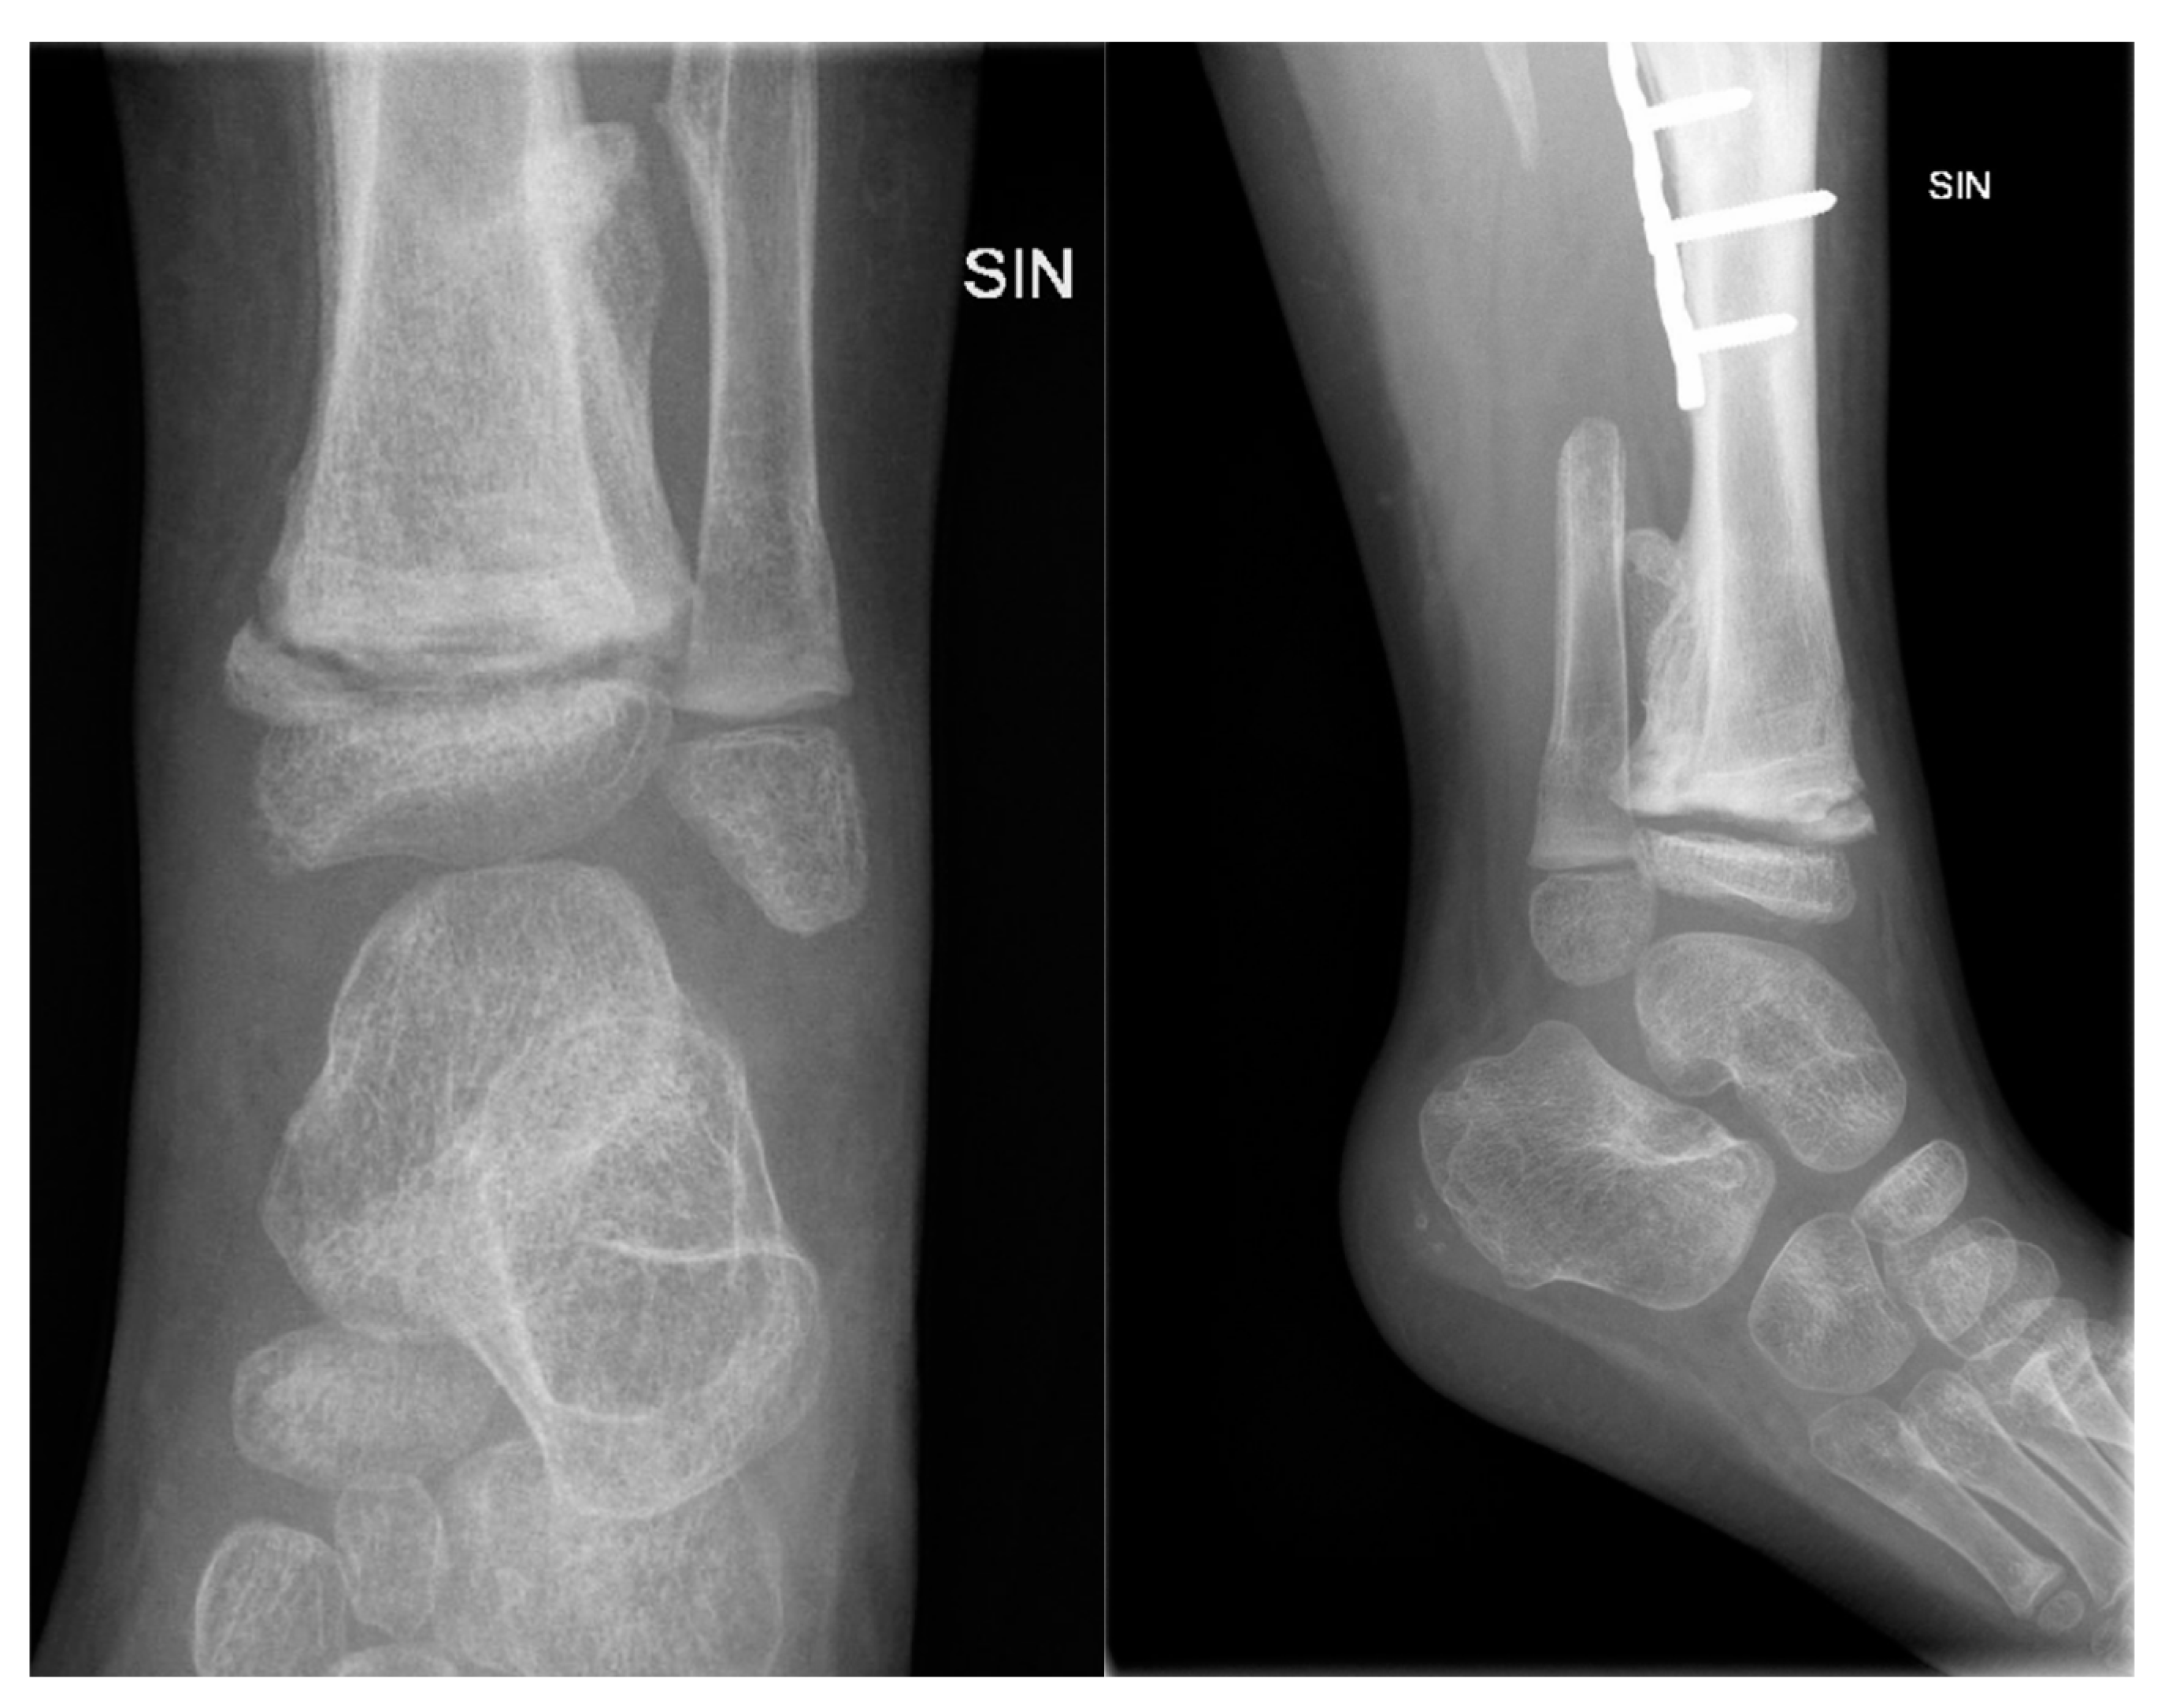

The patient was hospitalized due to an acute exacerbation of chronic osteomyelitis. Three months before this hospitalization episode, she returned to Ireland and injured her left lower leg and fractured the lateral and medial malleolus. The patient again fell in the children's playground, after a few days she refused to walk, and her parents noticed extensive swelling in her left ankle. 2 weeks later the patient's knee increased in size, and fluid accumulated in the knee joint (Figure 7).

She developed septic symptoms and was admitted to a hospital in Dublin, Ireland, where repeated interventions were done to drain the excess fluid. She also received antibacterial therapy (Rifampicin and Cefazolin). Radiological examinations were performed (X-ray, CT, magnetic resonance imaging (MRI)), showing extensive changes from the distal third of the thigh to the distal third of the calf. The inflammatory process was visible in the distal femur and proximal tibial growth zone. Wide areas of destruction were also observed, which included the ossifications forming around the left knee joint. Formation of massive ossification around the diaphysis of the tibia with no signs of convalescence in the bone itself (Figure 8 and Figure 9). MRI examination of the left knee was performed due to knee joint effusion, where an abnormal amount of fluid in the joint and signs of inflammation were determined.

Figure 8. The X-ray examination of the distal third of the thigh to the lower leg in AP and lateral projections reveals an inflammatory process in the distal femur and proximal tibial growth zone, wide areas of destruction, and massive ossification around the tibia diaphysis.

Figure 9. CT imaging shows an inflammatory process in the distal femur and proximal tibial growth zone, with wide areas of destruction, including the left knee joint bones, and massive ossification around the tibia diaphysis, without signs of convalescence.